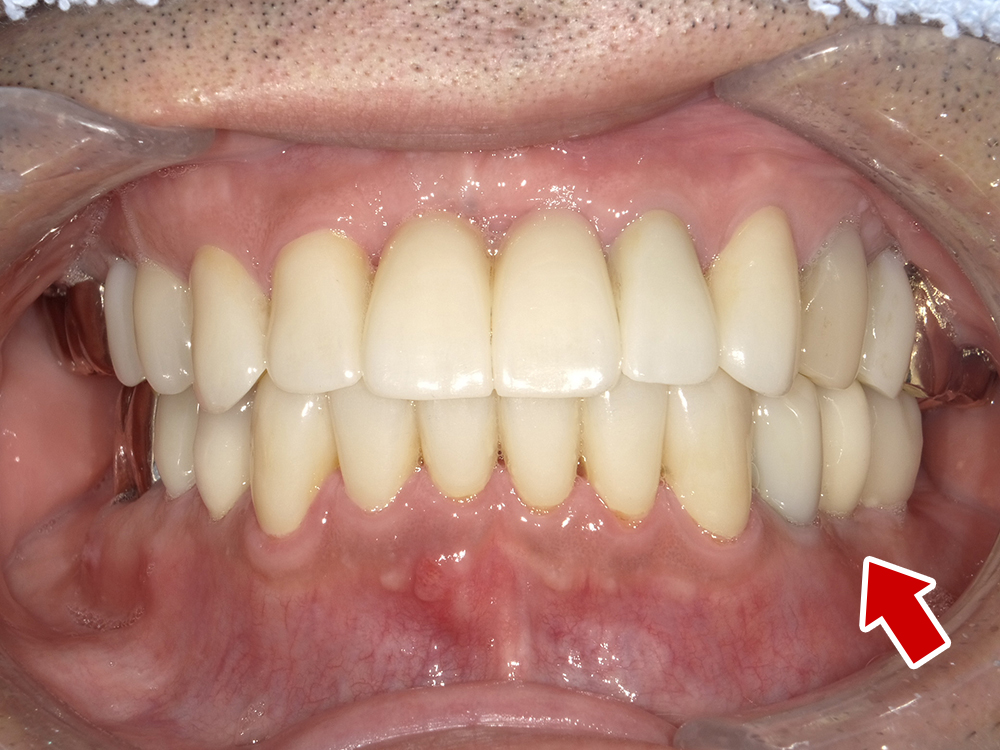

64歳 女性 紹介患者様

- 主訴

- 上下左右の歯が無くて、食べずらい、右下の歯が痛い

- 処置内容

- 右上3本、左上1本、右下3本、左下3本、鎮静麻酔

- 治療費用

- 上顎:約180万円(税込)下顎:約170万円(税込)

- 治療期間

- 上顎:約9か月、下顎:約6か月

- リスク

-

術後の腫れ、痛み(ピークは3日後、1週間で軽減)

上部構造物、仮歯の破折、人工歯根脱落リスクがあります